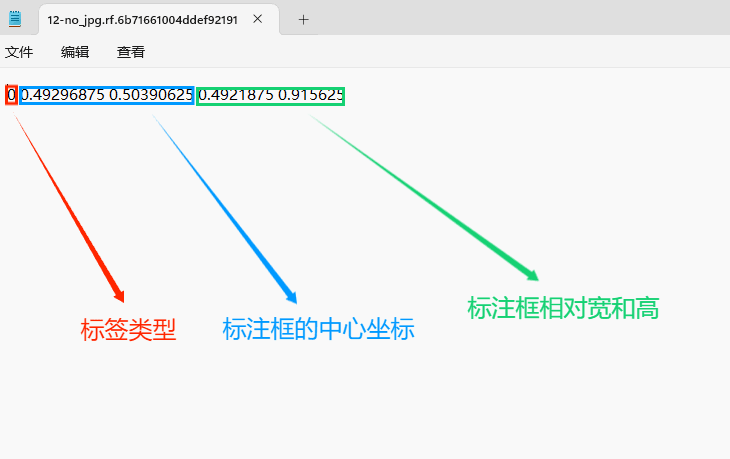

(4)YOLO模式创建标签的样式

存放标签信息的文件的文件名为与图片名相同,内容由N行5列数据组成。

每一行代表标注的一个目标,通常包括五个数据,从左到右依次为:类别id、x_center、y_center、width、height。

其中:

–x类别id代表标注目标的类别;

–x_center和y_center代表标注框的相对中心坐标;

–xwidth和height代表标注框的相对宽和高。

注意:这里的中心点坐标、宽和高都是相对数据!!!

存放标签类别的文件的文件名为classes.txt (固定不变),用于存放创建的标签类别。